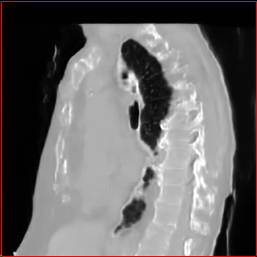

Figure 3 shows the generalizability of MAISI-v2 ControlNet for different body regions and voxel sizes. Figure 4 shows qualitative results for MAISI-v2 ControlNet on 5 types of tumors.

Chest Region

1×1×11\times 1\times 1

mm

384×384×384384\times 384\times 384

Abdomen Region

Figure 3: MAISI-v2 segmentation-guided results for small to large volume size and three different regions.